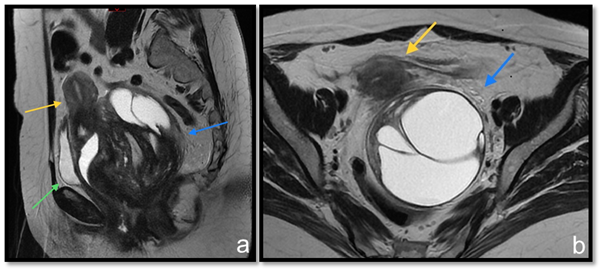

A 71-year-old woman developed clinically gluteal cellulitis. During the diagnostic investigation by transvaginal pelvic ultrasonography, a multiloculated pelvic solid and cystic lesion was detected, with septations and scarce blood flow to color Doppler (Figure 1). This exam couldn’t define the original site of this lesion. Pelvic magnetic resonance imaging (MRI) revealed a large pelvic solid and cystic formation with well-defined limits and an important cranial and anterior dislocation of the uterus and bladder (Figure 2). Retraction of the right ischiorectal fossa fat through the lesion and towards the pelvic cavity was detected (Figure 3) and represented a decisive information in the diagnostic investigation. Patient underwent surgical resection with complete excision of the tumor and evolved well in the postoperative (Figure 4). The histopathological examination revealed a neoplasm characterized by a densely collagenized stroma with alternating zones of cellularity, consisting of small spindled or ovoid cells with moderate amounts of eosinophilic cytoplasm and nuclei with fine chromatin and inconspicuous nucleoli, clustered around thin-walled capillaries (Figure 5). The immunohistochemical study revealed diffuse expression of desmin as well as estrogen and progesterone receptors, corroborating the diagnosis of angiomyofibroblastoma. There is no sign of tumor recurrence in periodic imaging exam less than one year after surgery.

Figure 2 T2 weighted MRI sequences at sagittal (A) and axial (B) planes. Pelvic expansive formation (blue arrow) promotes uterus (yellow arrow) and bladder (green arrow) displacement from their usual topography.